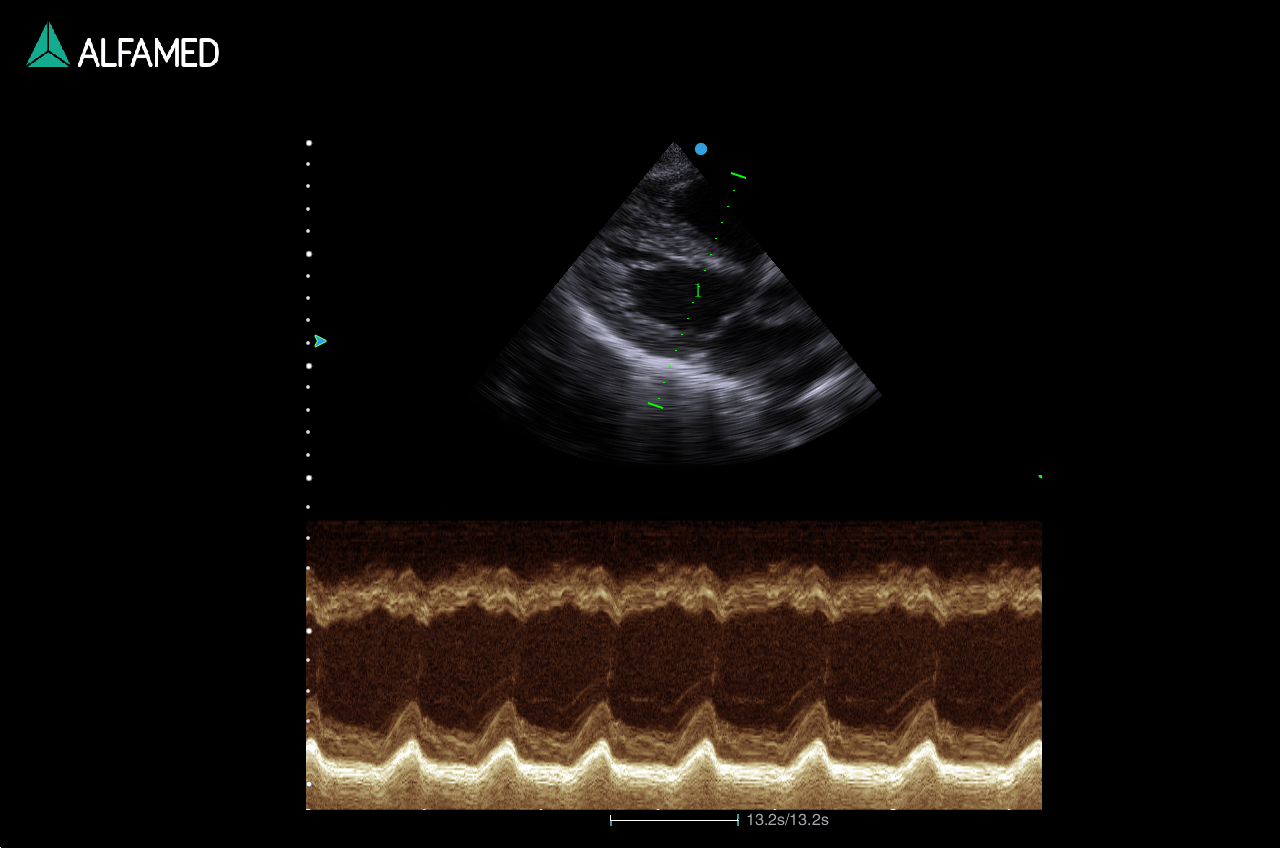

- 4D Pro (Qcut/Any Cut, nSlice)

- AMM

- TDI